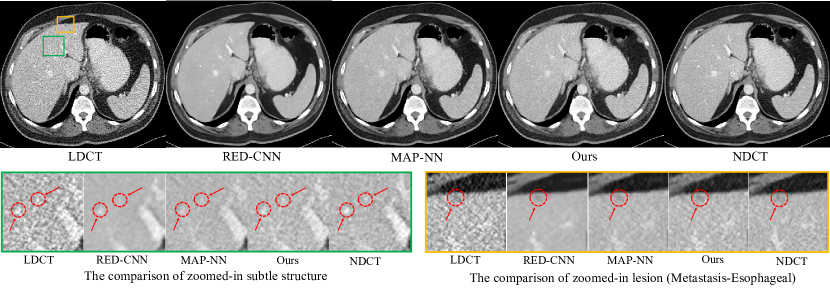

The analysis of visual results for zoomed-in subtle structure and lesion. Abdomen: As shown in Figure 10, we can make some important observations. First, the green box shows the comparison of zoomed-in subtle structure, we can find these structures (within red circles) nearly disappear for RED-CNN, due to the easily observed over-smoothness. Similarly, MAP-NN suffers from the same problem and also has a slight over-smoothness. Instead, our proposed model greatly preserves the subtle structure and generates the texture closest to NDCT. Both RED-CNN and MAP-NN only leverage the local information by the CNN, so it is difficult to balance the local detail and noise removal with limited information. Our proposed model adopts the framework of multi-information fusion such that extra information can be used as a supplement to produce the optimal results regardless of structure and texture. Second, as illustrate in the red circle of yellow box in Figure 10, our proposed model has the most obvious observation for the lesion (diagnosed as Metastasis-Esophageal), especially for the level of the grayscale. However, the lesion in RED-CNN and MAP-NN becomes very fuzzy. The superiority of lesion region further proves the effect of multi-information fusion framework. Chest: As shown in the yellow box of Figure 11, we can find that all models achieve the preservation of lesion (within the red circle). However, MAP-NN has more easily observed noise points compared with RED-CNN and our proposed model. RED-CNN losses the subtle structure basically as shown in red circle of green box. In summary, our proposed model has the most impressive visual performance, which naturally obtains the best performance of double-blind study as reported in Figure 8 and 9.